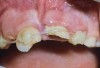

A healthy 8-year-old boy was referred for evaluation and treatment of his maxillary right and left central incisors (teeth Nos. 8 and 9). His dental history revealed that 10 days earlier these two teeth had been severely luxated and both crowns fractured. Emergency treatment that day included placement of a splint and performance of a pulpotomy on tooth No. 9.

The patient's endodontic examination revealed a flexible splint from teeth Nos. 7 through 10 (Figure 1). Tooth No. 8 had a 3 mm x 3 mm class II fracture of the mesioincisal portion of the crown. Tooth No. 9 had a class IV fracture of the crown running labiopalatally from the remaining 2 mm of the crown to bone level on the palatal. A pulpotomy had been performed on the exposed pulp. Both teeth exhibited class III mobility. Teeth Nos. 7 through 10 did not respond to cold testing. None of the teeth were tender to palpation, and only tooth No. 9 had a slight positive response to percussion. Periodontal probings of tooth No. 8 were 4 mm to 5 mm on both the labial and palatal aspects. There was a narrow 12 mm probing on the straight palatal of No. 9; the remaining probing depths were 4 mm to 5 mm.2 A periapical radiograph showed both teeth Nos. 8 and 9 to have incompletely formed roots with wide-open foramina (Figure 2).

Fig 1. Age 8. Facial view of teeth Nos. 8 and 9 at initial examination.

Figure 1